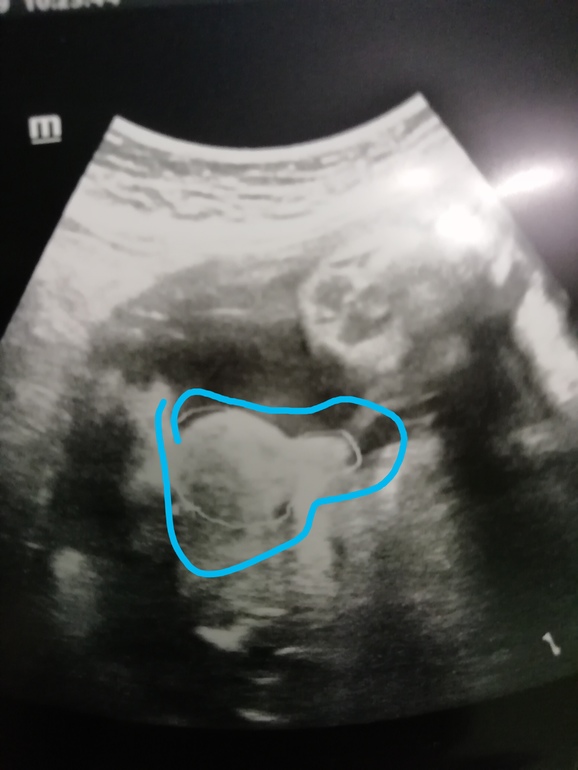

💙Ну а тут видно, что мужик 🥒